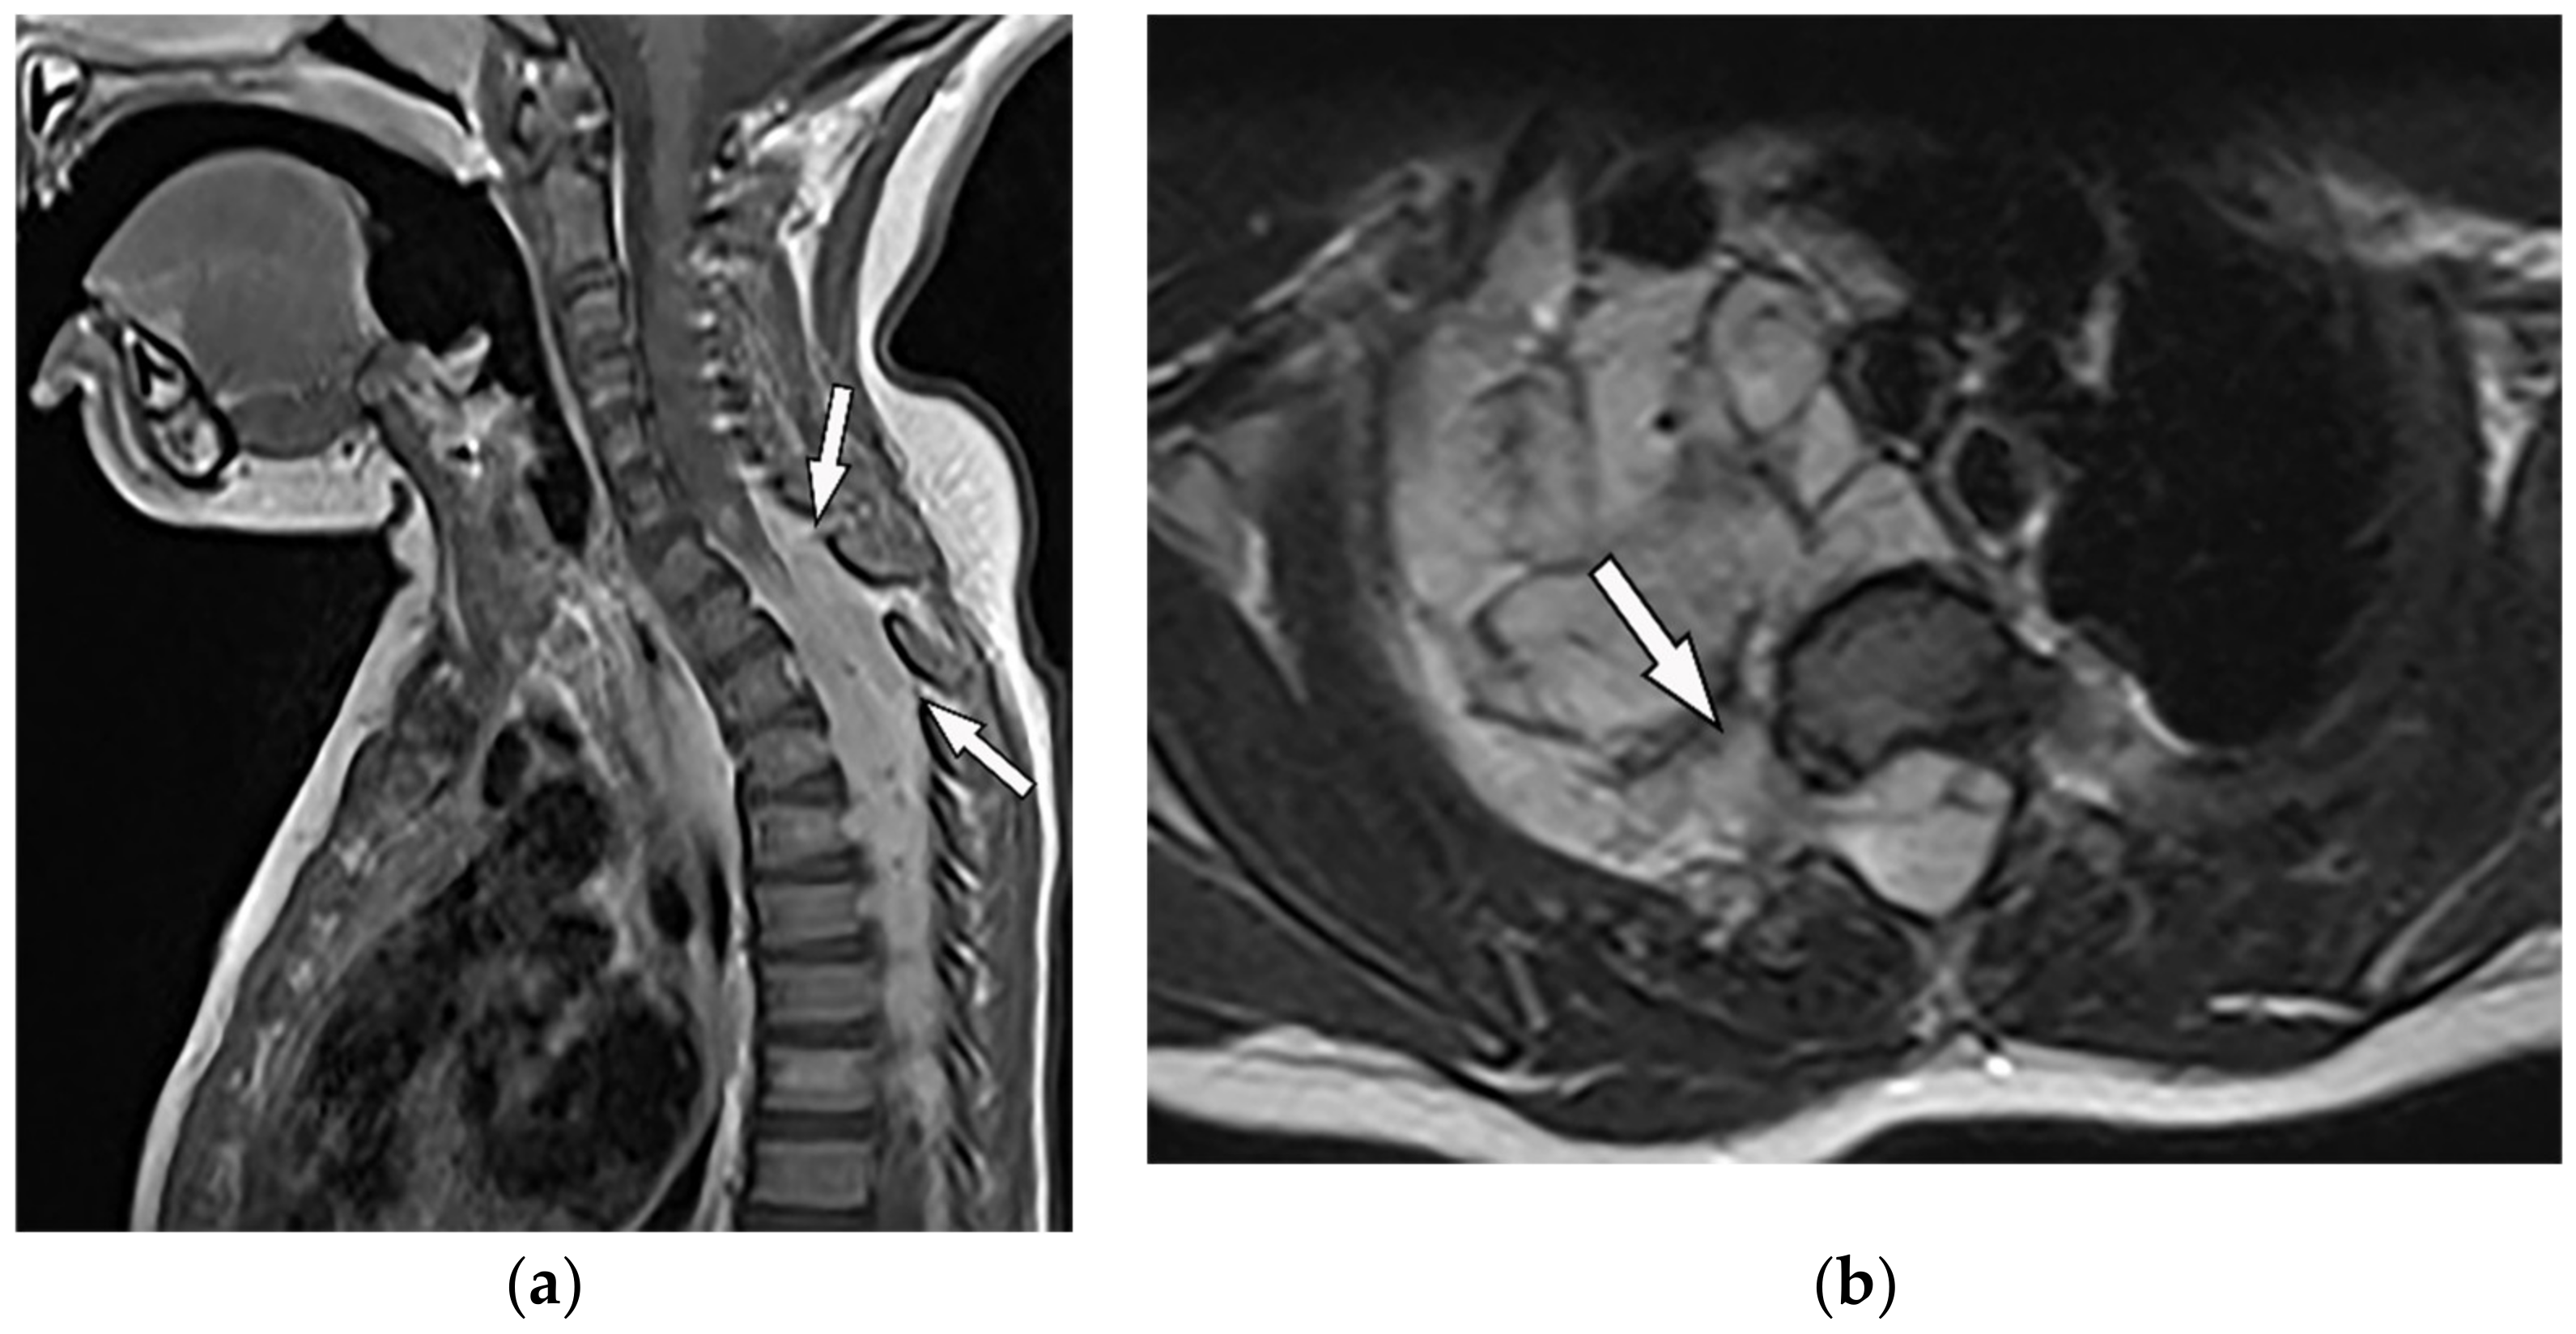

| Schwannoma | Well-defined mass with homogenous attenuation, “fat-split” sign, internal calcification in long-standing schwannomas, postcontrast enhancement except for areas of necrosis. | T1W: iso or slightly hyperintense; T2W: significantly hyperintense |